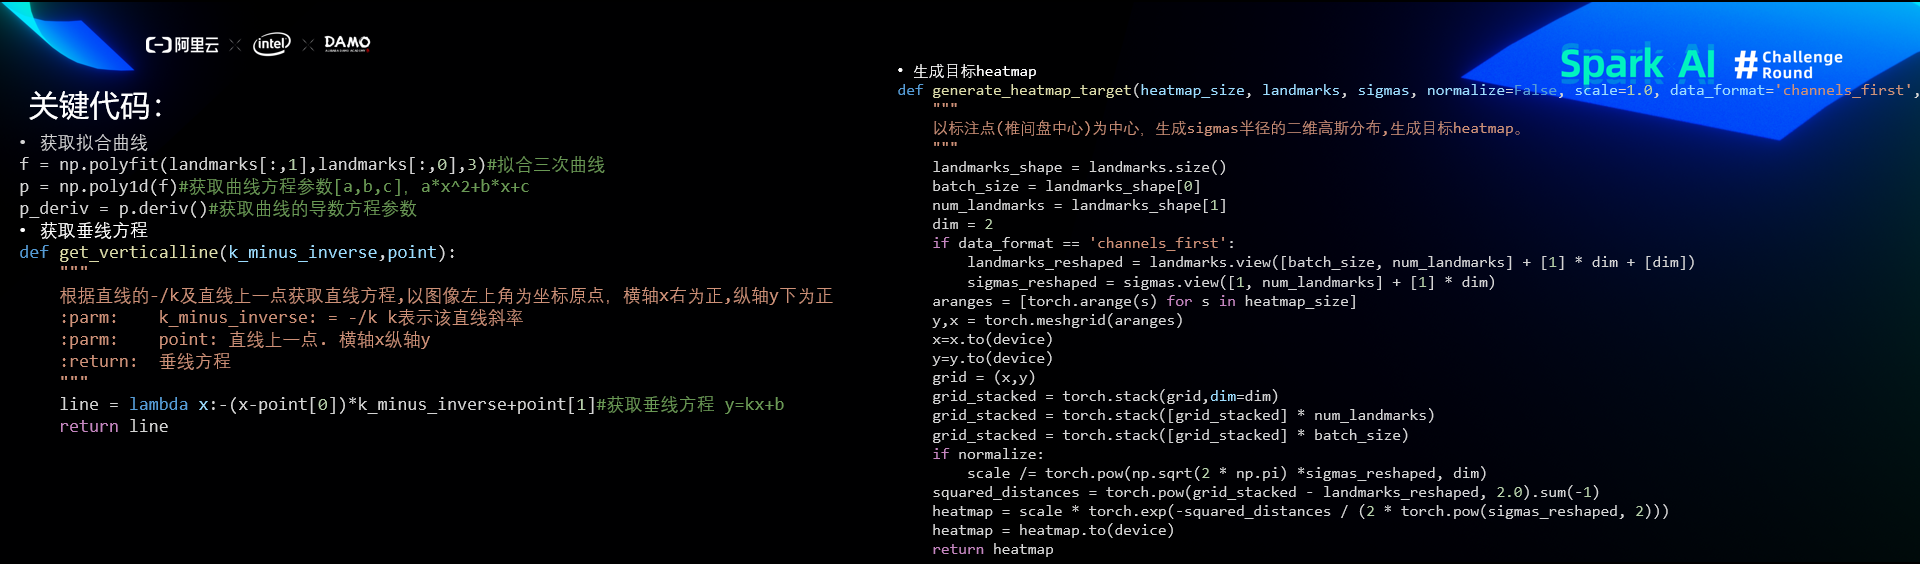

关键代码